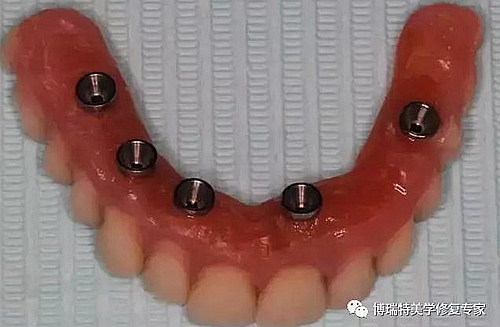

2.jpg

安裝臨時(shí)基臺(tái);

3.jpg

口內(nèi)在臨時(shí)基臺(tái)上固定臨時(shí)義齒;

取下臨時(shí)基臺(tái)和臨時(shí)義齒口外調(diào)磨修整;

4.jpg

患者口內(nèi)安裝臨時(shí)義齒,完成即刻修復(fù);